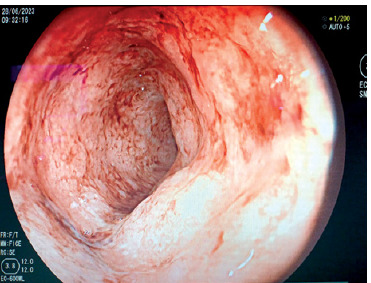

New challenges in the management of inflammatory bowel disease: a case study.